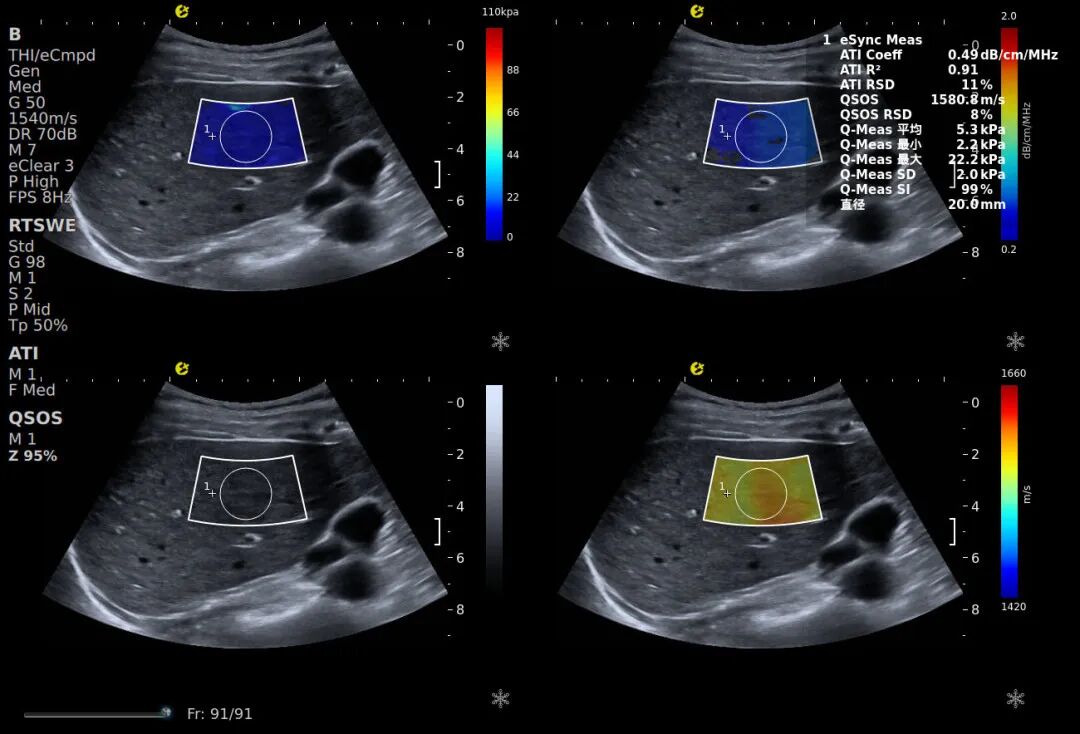

在这样的背景下,慢性肝病的早筛早诊成为护肝关键,而传统诊断方式的局限性却日益凸显。为破解这一临床困境,助力全国爱肝日“早筛防重症”的核心诉求,E超无创诊断设备凭借其技术创新,为慢性肝病无创筛查提供了全新解决方案。该设备区别于传统单一维度检测设备,E超构建了“硬度+脂肪+密实度+黏性”的四维定量评估体系,结合当前慢性肝病无创诊断的核心趋势(多参数联合评估),通过E成像(RTSWE®可精准量化肝脏硬度)、声衰减系数(ATI™)、声速定量(QSOS®)、黏弹性定量(QVisco™)四大参数的有机融合,实现了对肝脏病变的全方位解码,覆盖早期病变发现和肝纤维化、脂肪浸润等核心病变类型。

E成像-RTSWE®

通过精准量化肝脏硬度,为肝纤维化分期提供客观的kPa值依据(参考Baveno VII共识对肝脏硬度检测的相关标准),其鉴别F2期及以上纤维化的AUROC值达0.87,显著优于传统血清学指标(如FIB-4、APRI),相关数据来自多中心临床验证研究。

声衰减成像-ATI™

填补了脂肪浸润精准量化的临床空白,通过对超声信号衰减程度的定量分析,可清晰区分单纯脂肪肝与脂肪性肝纤维化。该参数可有效解决肥胖患者肝脏检测失真的行业难题,而肥胖引发的代谢紊乱,正是临床中MASLD的核心诱因之一。

声速定量成像-QSOS®

作为早期损伤“探测器”的QSOS®声速定量技术,通过捕捉肝脏实质内声波传播速度的细微变化,能在纤维化萌芽阶段就发出预警,弥补了传统技术对早期肝损伤的漏判短板。